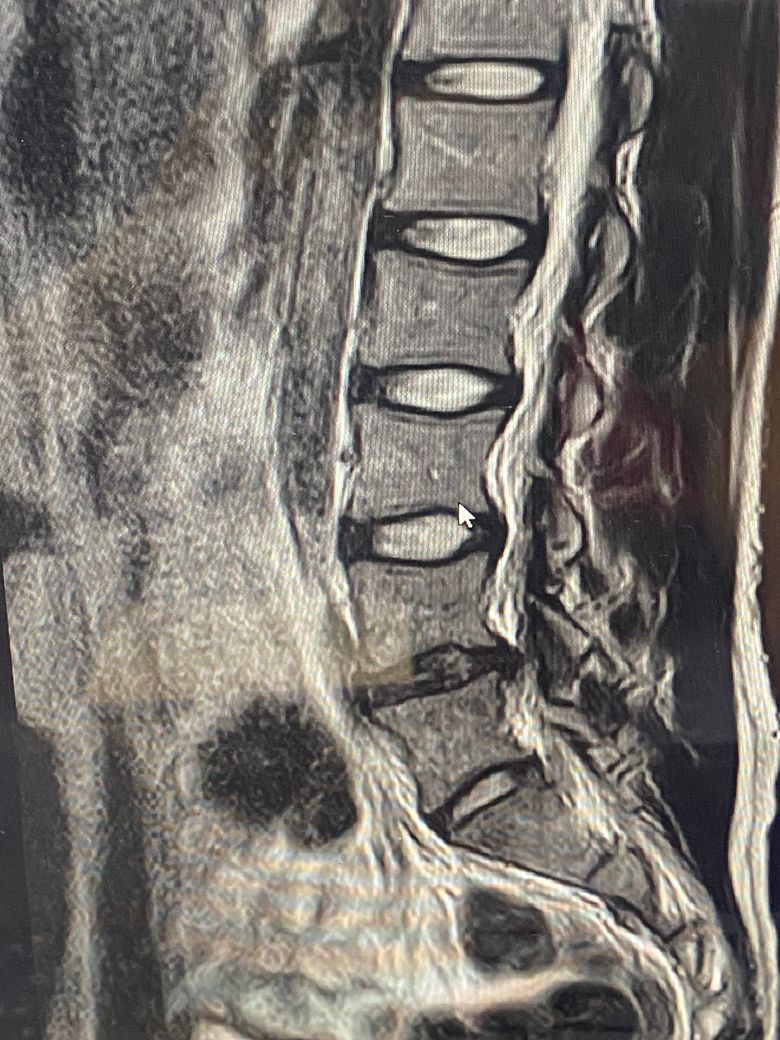

• 2번 째 사진

MRI는 3컷만으로 평가할수 없지만 현 상태상 허리 디스크 탈출증이 의심됩니다.

• MRI 단면 몇 장으로 정확하게 상태를 평가하기는 어렵지만 요추 4번의 디스크 돌출 및 그로 인한 척수의 눌림이 발생한 것으로 사료됩니다. 방사통이 있는 상태에서는 심한 운동을 할 때에 디스크 증상을 오히려 악화시킬 수 있기 때문에 현재 상태에서 바로 헬스를 하시기 보다는 식이요법과 걷거나 가볍게 뛰는 정도의 운동을 통해서 체중 감량을 하시고 통증에서 자유로워 지면 그 때에 피트니스나 필라테스 등을 통해서 직립근 등 코어 근육을 강화해주시는 것을 추천드립니다.